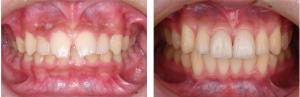

※術前(左)と術後(右)

治療後の結果について、患者さまから前向きなお声をいただいています。